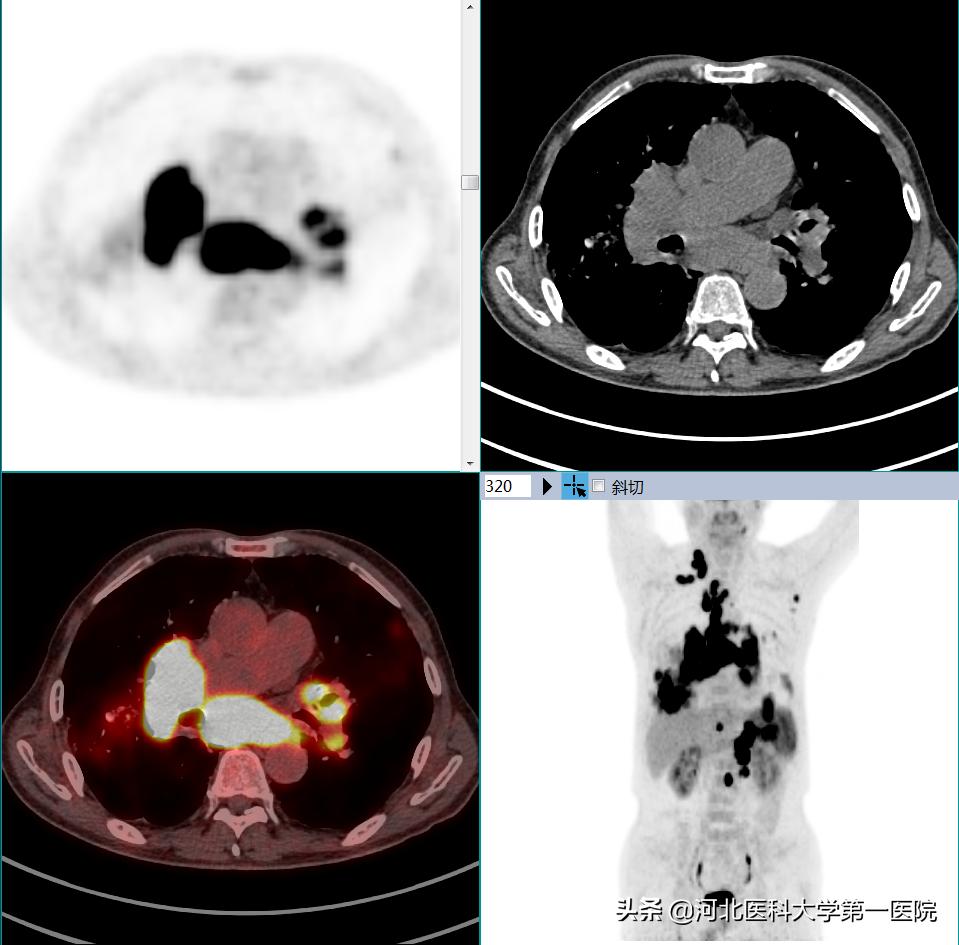

经人介绍,段大爷来到河北医科大学第一医院就诊,经过详细问诊后,医生建议做PET-CT进一步检查。于是在住院第2天,段大爷便到核医学科进行全身PET-CT检查,检查结果显示段大爷双肺有多发大小不等结节状及片状高密度病变,双侧肺门、纵隔、双侧颈部、右侧锁骨上窝、左侧腋窝、腹膜后有多发淋巴结,部分肿大并且融合成团,并且这些病变均有明显的FDG高摄取。

结合临床表现,综合考虑段大爷患有恶性肿瘤性病变,淋巴瘤的可能性非常大。据此,临床医生很快为段大爷安排了经皮右肺病变活检穿刺,最终病理结合免疫组化证实为非霍奇金淋巴瘤(弥漫大B细胞淋巴瘤),肺内病变是淋巴瘤引起的肺浸润。